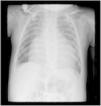

We report the case of a four-month-old infant with Down's syndrome referred for observation due to progressive tachypnea and failure to thrive. Chest radiography revealed cardiomegaly and pulmonary congestion (Figure 1). Transthoracic echocardiography showed severely dilated left-sided chambers with global systolic dysfunction, but was inconclusive regarding the underlying abnormality due to the patient's poor acoustic window (Figure 2). On cardiac catheterization, the child was found to have a 10 mm long, 3.8 mm wide patent ductus arteriosus, anatomically unsuitable for percutaneous closure, and a hypoplastic left coronary artery (Figure 3). The patient underwent an uneventful surgical ligation of the ductus via lateral thoracotomy and was discharged after six days. One month later, the child was admitted to the pediatric ICU with respiratory failure requiring mechanical ventilation. Transthoracic echocardiography revealed a severely dilated left ventricle with dyskinesia of the posterior and lateral walls. Due to lack of clinical improvement, a cardiac computed tomography was performed, revealing a large type I aortopulmonary window (10 mm×10 mm) between the right aspect of the distal pulmonary trunk and the left aspect of the ascending aorta (Figure 4). After surgical closure with an aortic cuff, the patient presented gradual clinical recovery until discharge with residual systolic dysfunction and tachypnea. Through careful analysis, the aortopulmonary window was found to be already visible on the catheterization cines, but was probably overlooked due to the concomitant ductus. The authors wish to highlight that, even in the presence of a common congenital heart defect, additional abnormalities must always be carefully excluded.